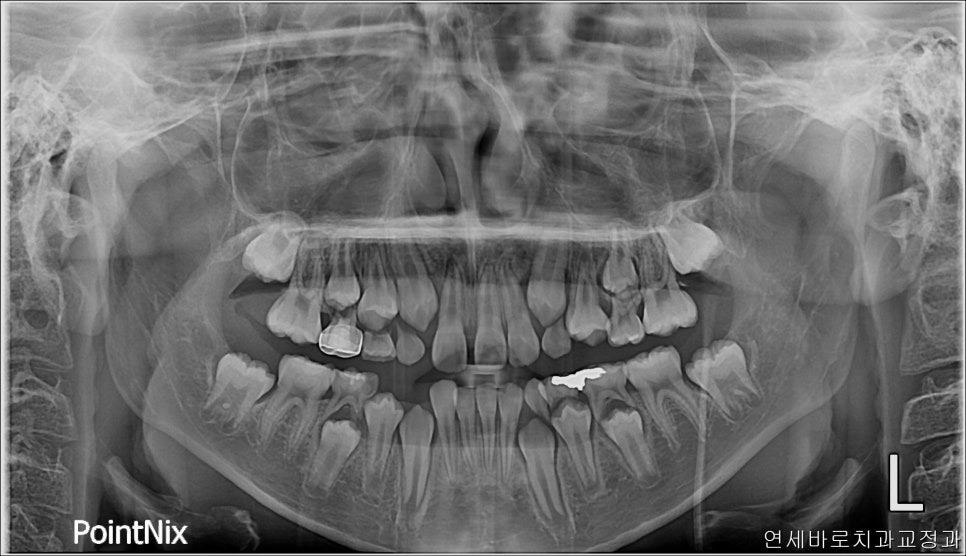

처음 우리병원 왔을때 사진입니다

여기 오른쪽 두번째 앞니가 없는것이 발견되었습니다.

얼굴 전체의 중심선과도 많이 벗어난 모습입니다.

위아래 치아끼리의 중심선은 안맞아도, 위치아의 중심선과 얼굴 전체의 중심선은 일치하는 것이 보기 좋습니다.